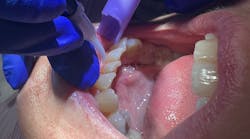

- Treatment of soft tissue lesions, cold sores, aphthous ulcers, and denture sores

Accelerated tissue repair and cell growth: photons of light from lasers penetrate deeply into tissue and accelerate cellular reproduction and growth. Laser light increases the energy available to the cell so that the cell can take on nutrients faster and get rid of waste products. The result is that damaged cells are repaired faster.

Faster wound healing: laser light stimulates fibroblast development in damaged tissue. Fibroblasts are the building blocks of collagen, which is the protein required to replace old tissue and repair tissue injuries.